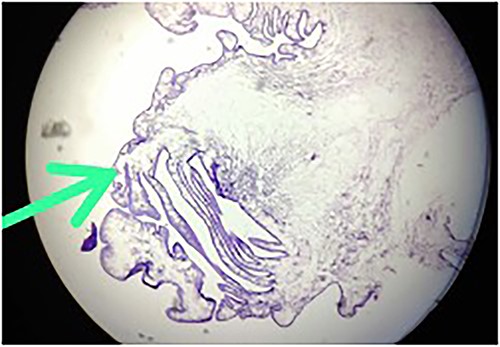

The histopathology report revealed the presence of a parasite composed of cuticle, subcuticular cells along with muscle, and chronic inflammatory infiltrate with a final impression of cysticercosis (Fig. 5). After this diagnosis, we reevaluated our history with more details. There was no history of headaches, seizures, or visual difficulties. The patient was found to be a vegetarian in diet. A pediatric physician evaluation was also done where a contrast-enhanced computed tomography (CECT) brain and ophthalmic examination were advised to evaluate for a possibility of neurocysticercosis. The ophthalmic examination was within normal limits, but the CECT showed a hypodense area in the right frontal lobe (Fig. 6). On further correlation with contrast MRI, a ring-enhancing lesion in the right paramedian frontal lobe surrounded by non-enhancing vasogenic edema was seen. Another small lesion was seen in the right external capsule surrounded by minimal edema (Fig. 6). Both lesions appeared to be granulomatous, giving an impression of neurocysticercosis. The child was treated with syrup albendazole 15 mg/kg per day in two divided doses for 1 month. A short course cover of dexamethasone 0.1 mg/kg per day started 1 day before albendazole was started, continued for a month, and then tapered over a week.

Hematoxylin-and-eosin-stained histopathology slide, showing cuticle, with subcuticular cells and chronic inflammatory infiltrate suggestive of cysticercosis.